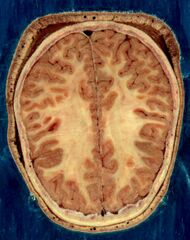

![]() The human brain, obtained after an autopsy | |

The cerebrum, brainstem, cerebellum, and spinal cord are covered by four[11] membranes called meninges. The membranes are the tough dura mater; the middle arachnoid mater and the more delicate inner pia mater. Between the arachnoid mater and the pia mater is the subarachnoid space and subarachnoid cisterns, which contain the cerebrospinal fluid.[12] The outermost membrane of the cerebral cortex is the basement membrane of the pia mater called the glia limitans and is an important part of the blood–brain barrier.[13] The living brain is very soft, having a gel-like consistency similar to soft tofu.[14] The cortical layers of neurons constitute much of the cerebral grey matter, while the deeper subcortical regions of myelinated axons, make up the white matter.[7] The white matter of the brain makes up about half of the total brain volume.[15]

The outer part of the cerebrum is the cerebral cortex, made up of grey matter arranged in layers. It is 2 to 4 millimetres (0.079 to 0.157 in) thick, and deeply folded to give a convoluted appearance.[20] Beneath the cortex is the cerebral white matter. The largest part of the cerebral cortex is the neocortex, which has six neuronal layers. The rest of the cortex is of allocortex, which has three or four layers.[21]